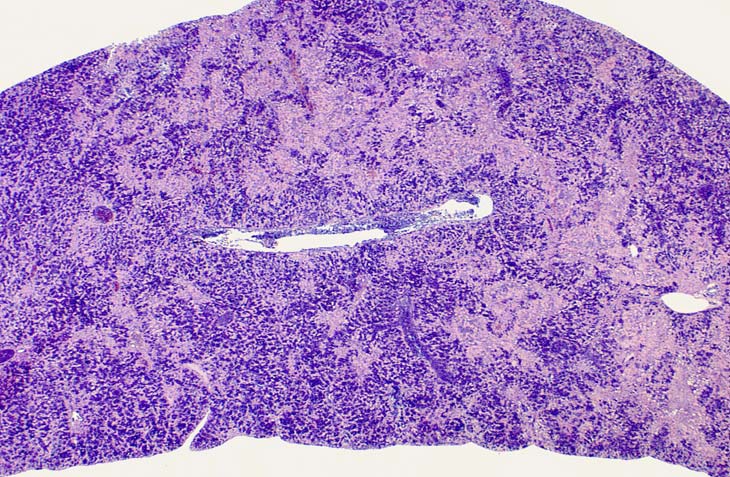

Low magnification of erythroleukemic infiltrates in the liver.

Examples of erythroleukemia in a Tg.AC mouse.